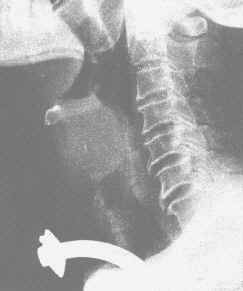

椎前軟組織陰影可增寬,氣管被推向前方或偏於一側,當膿腫穿破可見含氣積液腔。晚期膿腫可見鈣化影。

頸椎結核起病時X線表現多不明顯,一般在發病數月至1年才有陽性發現。中心型病灶早期表現為在一個或可在兩個鄰近的椎體中央骨松質中出現破壞透亮區,邊緣模糊,周圍一般無明顯骨質增生現象。隨著病變的發展,可見破壞區逐漸擴大,可以均等地向上、下兩方擴展,或者以向一方破壞為顯著如破壞嚴重,可使椎體產生相應的塌陷變扁。當結核病灶侵及其附近的椎間盤時使椎間隙變狹,如穿過椎間盤而侵及鄰近的椎體時可見累及的一面骨質破壞。邊緣型病灶早期表現為椎體前緣、上緣或下緣出現骨質破壞,常伴有附近的椎間隙狹窄。這種病變多見於成人,病變一般發展較慢,有局限於兩個椎體的傾向,中間的椎間隙可有明顯的狹窄,兩面的椎體有不同程度的破壞,有時可呈局限的缺損,類似許氏結節的表現。如果一個椎體的一面破壞嚴重,則其鄰近的無明顯破壞的椎體可以嵌入破壞區。骨膜下型病灶較為典型的表現為一、二個椎體旁有明顯的膿腫形成,但椎體無顯著的破壞,僅周圍與膿腫相鄰部位邊緣不清或不甚規則,椎間盤保持正常。其後在椎體前緣出現骨質侵蝕而凹陷,往往須用體層攝影才能清楚顯示。局限於椎弓、棘突和橫突的結核病灶甚為少見,表現為受累部位的骨質破壞,在其附近出現軟組織腫脹陰影。寰樞關節結核則須攝開口位頸椎片。早期僅顯示寰樞關節脫位或半脫位,而無骨質破壞。後期可見側塊、齒狀突被破壞,甚至見到齒狀突骨折。